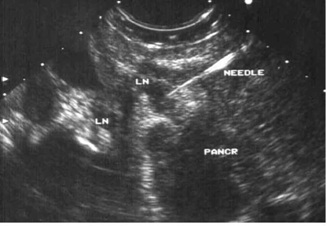

בהכוונת ה-EUS אפשר להחדיר מחט לשאת או לבלוטה ולקחת בדיקה ציטולוגית מהם (תצלום 26.9).

ביופסיה הנלקחת מבלוטת לימפה בהכוונת EUS

(לבלב = Pancr, בלוטת לימפה = LN, מחט הביופסיה = Needle)

10. דיקור הלבלב במחט עדינה (FNA) - בהדרכת טומוגרפיה ממוחשבת או אולטרה-סאונד אפשר להחדיר מחט עדינה דרך הבטן לנגע בלבלב ולקבל דגימה לבדיקה ציטולוגית. רגישות הבדיקה היא 85%, וסגוליותה (ספציפיות) קרובה ל-100%. אולם תוצאה שלילית אין בה כדי לשלול לחלוטין שאת ממארת בלבלב (תצלום 26.9) (תרשים 4.9).